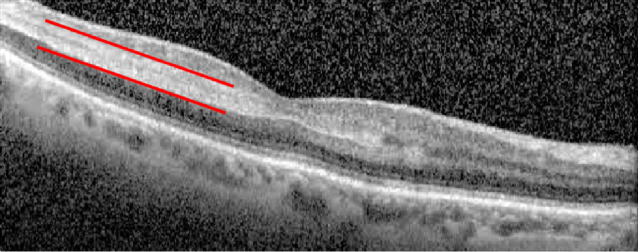

Giant cell arteritis (GCA) is the most common vasculitis of large and medium vessels affecting adults over the age of 50. Due to its acute ischemic damage through a systemic inflammatory process, GCA is a medical emergency with the risk of permanent vision loss. Therefore, early intervention is critical. Patients often present with well-documented systemic manifestations such as jaw claudication, headache, scalp tenderness, and fatigue. These patients are usually subject to blood tests for inflammatory markers and temporal artery biopsy. However, clinical manifestations vary considerably and may masquerade as neuro-ophthalmic manifestations that are not pathognomonic of GCA. We conducted a review to discuss documented neuro-ophthalmic manifestations and provide insight into the rare presentations to help avoid pitfalls in its diagnosis. Findings from the included articles were sorted into afferent and efferent neuro-ophthalmic manifestations. According to our literature review, the main afferent manifestations documented are ischemic optic neuropathy, retinal artery occlusion, choroidal infarction, ocular ischemic syndrome, orbital inflammatory syndrome, and strokes causing visual field loss. The efferent manifestations include cranial neuropathy (3 rd , 4 th , and 6 th ), extraocular muscle ischemia, and internuclear ophthalmoplegia. Other rare causes are tonic pupil from ciliary ganglion involvement, uveitis, and encephalopathy. If GCA is suspected, in addition to inquiring about systemic symptoms and doing a complete neuro-ophthalmic exam, these patients should be sent for inflammatory serological markers, as well as temporal artery biopsy (TAB). If clinical suspicion remains high, high-dose steroids should be started immediately.